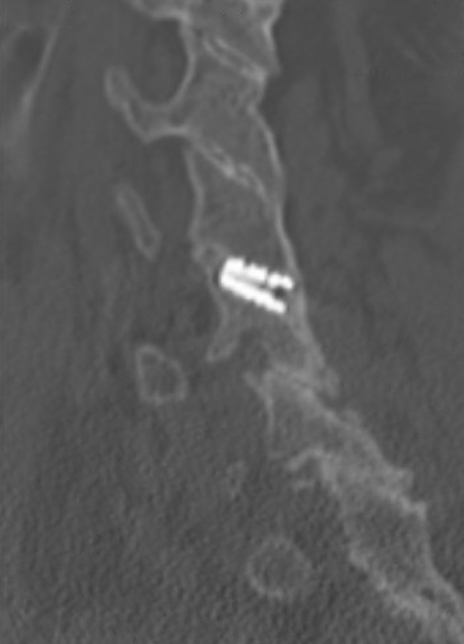

Sagittal CT image showing right anterior/posterior bone bridging.